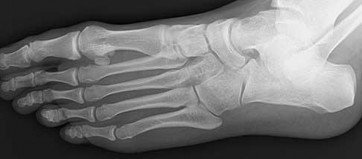

Figures 2a through 2h

Calcaneonavicular (CN) coalition

Talocalcaneal (TC) middle facet coalition

TC posterior facet coalition

- Calcaneonavicular (CN) coalition

Tarsal coalitions occur when primitive mesenchymal cells fail to differentiate and form the

normal articular separations between the tarsal bones of the hindfoot. Overall incidence is difficult to determine because many affected people are minimally symptomatic or asymptomatic. Symptomatic tarsal coalitions typically present in adolescents as a painful flatfoot; however, there are a number of possible presentations, and occasionally symptoms do not appear until adulthood. Most tarsal coalitions are between the calcaneus and the navicular (CN) and the talus and the calcaneus (TC). Although most TC coalitions are across the middle facet, posterior facet coalitions do occur. Plain radiographic evaluation of suspected tarsal coalition is the mainstay for diagnosis. However, coalitions can be bony or fibrous, and making the diagnosis can be difficult. The addition of CT images to distinguish bony definition and MR images to decipher soft tissue can aid in diagnostics. Bony coalitions appear as definite bony bridging between the bones, while fibrous coalitions are suspected when distortion of the bony anatomy is seen. Bony coalitions are best seen on the oblique view (CN) and Harris axial view (TC). There are a number of secondary signs such as the anteater (AE) sign (elongation of the anterior process of the calcaneus as it extends to the navicular as seen on the lateral view [CN]). talar beaking (traction spur of the talar neck thought to result from abnormal stresses as seen on the lateral view [both CN and TN]), and the “C” sign (a continuous cortical contour from the medial talus to the sustentaculum tali [ST]) as seen on the lateral view (TC). A number of newer signs are not as well known, such as a broad mediolateral dimension of the navicular on the anteroposterior (AP) view (the

navicular is wider than the talar head [CN]), nonvisualization of the middle facet on the lateral view (TC), the brick sign (a normal ST is flat, but a distorted ST is enlarged and curved [CN]), and a tapered lateral navicular bone as seen on the AP view (the medial navicular [CN] is much thicker than the lateral navicular).

Figure 2a shows an irregularity of the anterior calcaneus. Figure 2b shows TB, AE, and MF. Figure 2c is an oblique view and shows nothing specific. Figure 2d shows an MF. Figure 2e shows an AE. Figures 2f, 2g, and 2h show edema and an abnormal connection between the calcaneus and the navicular, all consistent with a CN coalition.